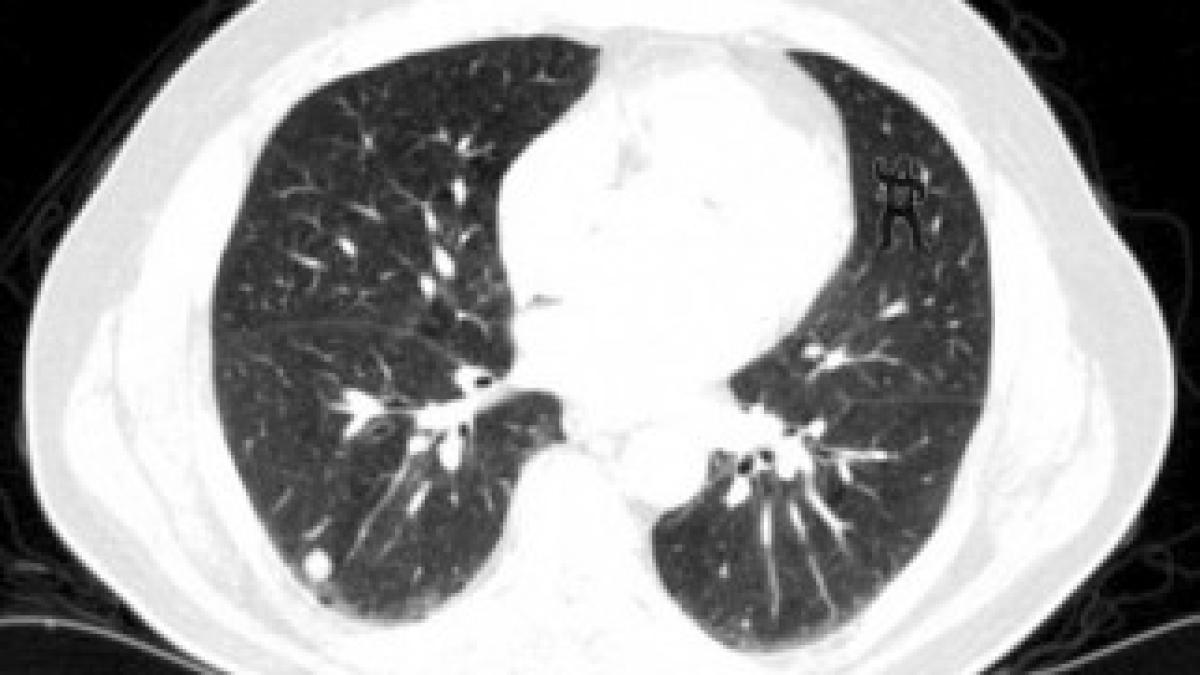

Cercetătorii au recurs la acest nou studiu psihologic pentru a descoperi consecințele „orbirii involuntare”, atunci când nu vezi ceva ce este în faţa ta. Pentru studiu, oamenii de știință au rugat 24 de radiologi să se uite la câteva radiografii făcute la cinci bolnavi de cancer pulmonar, scrie Daily Mail.

Patru dintre pacienţi aveau radiografiile curate, dar erau ascunse într-o grămadă de 239 de imagini de la un al cincilea pacient, unde cinci radiografii consecutive arătau şi o gorilă care dansează.

Doar patru dintre participanții la studiu au observat gorila care dansează. Gorila a fost observată de doar patru dintre cei 24 de radiologi care au fost rugaţi să examineze radiografiile a cinci pacienţi diferiţi. Pentru a face testul mai greu, în prima radiografie, gorila avea o transparenţă de 50%. În următoarea era de 75 de procente, iar în a treia avea vizibilitate maximă. În ultimele două fotografii, vizibilitatea a fost redusă la jumătate.

Astfel și radiologii de la spitalul din Boston, atenți să identifice nodulii de ancer pe radiografii, ei nu au reușit să vadă și gorila care dansează, deși dimensiunea sa era de 48 mai mare decât cea a nodulilor.